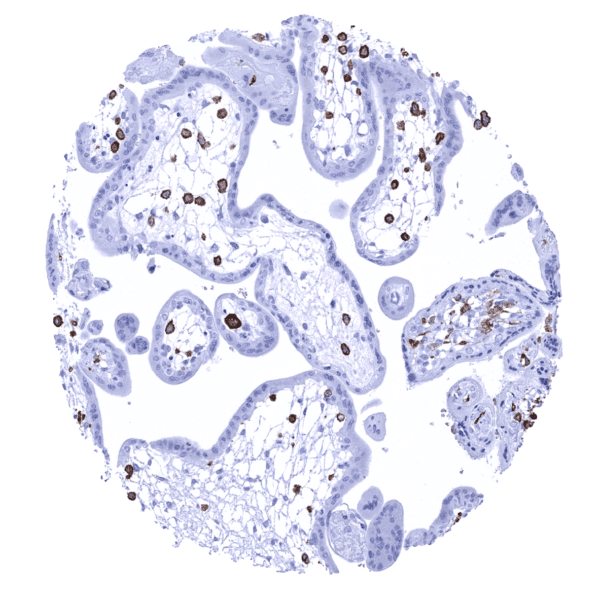

AIF1 immunostaining is seen at varying levels of intensity in histiocytes/macrophages in various different tissues. The staining is mostly moderate to strong but varies depending on the location of cells and also between different samples from identical tissues. For example, AIF1 immunostaining is considerably weaker in dendritic cells/macrophages of the germinal centre than in macrophages of the interfollicular area in lymph nodes and tonsils. AIF1 expression can be particularly strong in Kupffer cells in the liver, placenta macrophages (variable between samples), lung, and the adrenal gland. In the brain, a variable staining of microglia occurs, ranging from low to high intensity. Granulocytes also stain AIF1 positive. In the kidney, a moderate to strong membranous staining of glomeruli is seen. This reflects the only AIF1 staining of non-immunological cells in normal adult tissues.